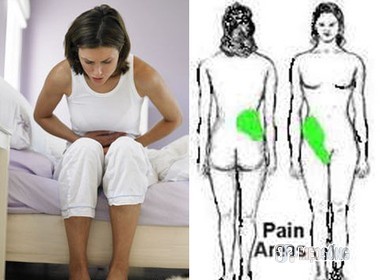

2. Phòng chống sỏi thận

Sỏi thận thường được hình thành từ canxi, một khi chúng phát triển thành những viên sỏi, thì hoặc chúng sẽ đi qua niệu đạo hoặc sẽ làm phá vỡ tình trạng khoẻ mạnh của cơ thể. Bất kỳ ai bị sỏi thận đều có thể có nguy cơ trải qua tình trạng đau đớn khủng khiếp. Lợi ích to lớn nhất mà bạn có thể thu được là uống khoảng 1 lít nước ép bưởi mỗi ngày.